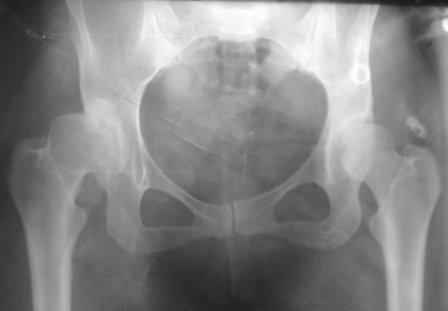

При определении показаний к м/в остеотомии учитываем не только функциональное состояние, но анатомическую форму сустава. Например, при той форме, что на картинке в вашем письме (мелкая впадина,уже не сферичная головка)НИИТО вполне обосновано предлагает ТЭП. Варизирующая остеотомия в "чистом виде" усилит конфликт в опорной зоне сустава. Если очень "настоятельно просит" - экстензия с наружной ротацией по R.Bombelli. То есть на открытом суставе бедро согнуть и ротировать внутрь до покрытия головки впадиной. Сформировать канал через шейку в головку с тем расчетом, что после м/в распила бедро нужно вывести в функциональное положение. Фиксировать 90 град. медиализирующей ортопедической пластиной с клинком. Но выздоровления не обещать, покрытие головки малое, длительного эффекта не будет. Нужна периацетабулярная остеотомия или пластика крыши, но это другая сложность и другая травматичность. Необходимость ТЭП оттянете лет на 10 в лучшем случае. Надо учитывать, что в этом случае ТЭП операция не первая, это увеличивает инфекц. риски и снижает функциональный результат для сустава. Я бы рекомендовал трость с противоположной стороны, ЛФК на приведение, чтобы подрос оссификат крыши и сформировались оссификаты головки. При нормотрофическом типе поражения можно будет провести вальгизирующую остеотомию, эффект которой более длительный или больная за это время найдет возможности приобретения ЭП.

Данный сустав в начальной стадии разрушения, но все-таки я бы сделал обзорный таз и отдельные снимки сустава в 30 градусной абдукции и аддукции. Также снимки с внутренней и наружной ротацией для оценки состояния головки бедра.

Представляю Р-снимки: обзорная, с отведением и с приведением.

Глубокоуважаемый Абдурашид. Здесь нет снимка с отведением. Если Вы сами сходили в рентгенкабинет и лично отвели пораженную конечность максимально возможно, а также дали максимально возможную внутреннюю ротацию-это одно!!!! Значит у пациентки тяжелейшая приводящая контрактура тазобедренного сустава!! И необходимо разобраться-миогенная или артрогенная? Если же Вы просто назначили указанный снимок и доверили произвести укладку рентгентехнику-это другое!!! Одному богу известно, что она делала, ведь на р-снимке отведения нет!

Все предыдущие корреспонденты предлагают вам достаточно простую вещь-смоделировать предлагаемую Вами операцию (т.е. дать отведение и внутреннюю ротацию) и посмотреть, как изменятся соотношения в суставе. Не обижайтесь, но судя по представлению клинического случая угловые величины, характеризующие пространственные соотношения в тазобедренном суставе, ваши рентгенологи не считают.

Уважаемый Игорь Владимирович. диссертации М М Камоска, и В Е Баскова я нашел, но почему-то не могу открывать, и еще в данном случае имеется дисплазия т/б за счет недоразвития крыши в/впадины да и всей подвздошной кости, маргинального вывиха или латеропозиции головки вследствие лечебных ощибок нет, головка стоит на месте. Р-граммы сделал сам, но почему-то у больной отведение и внутренная ротация стали очень болезненной, и сухожилия приводящих мышц сильно натягивается.(контрактура артро-миогенная).

Глубокоуважаемый Игорь Владимирович! Признаюсь допустил ошибку, из-за напряженности работы и нехватки времени, когда повторно внимательно посмотрел все понял и не успел исправить ошибку до Вашего поста, конечно скошенность крыши в пределах 40гр,часть головки кнаружи линии Омбредана-Перкинса , облитерация дна вертлужной впадины и т.д.-это ДМВБ.